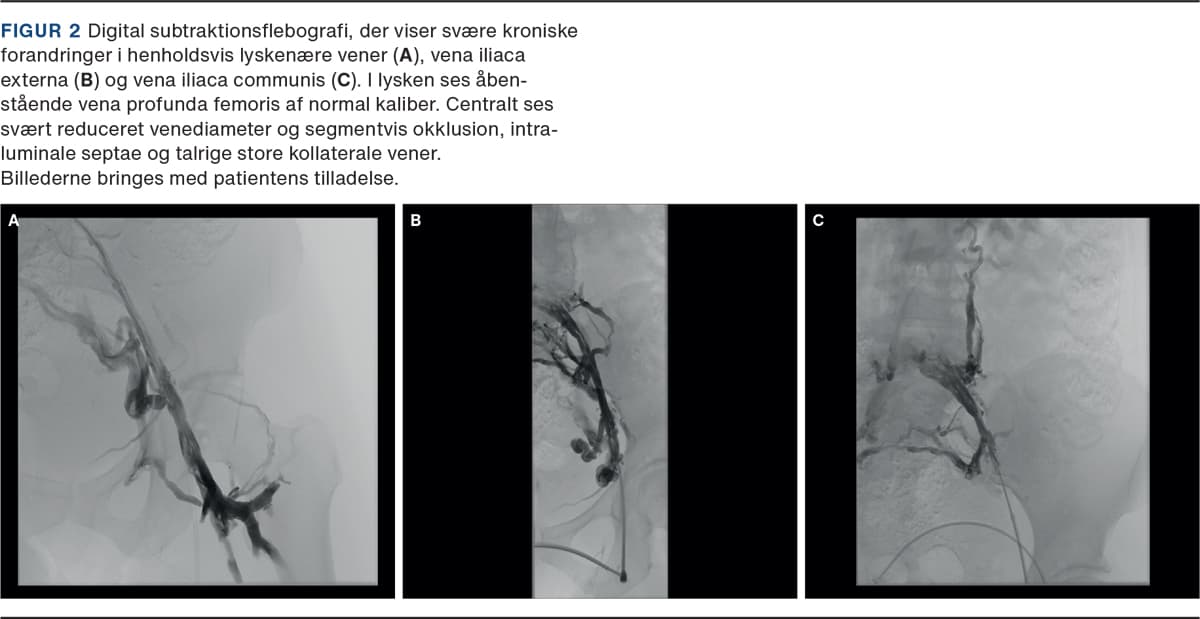

Endovaskulær behandling, dvs. ballondilatation og stentning, udføres for at genetablere det centrale venøse afløb fra ekstremiteten. Indsættelse af en stent forudgås af prædilatation af det obstruerede venesegment med højtryksballon og efterfølges af efterdilatation af selve stenten, ligeledes med højtryksballon (Figur 2 og Figur 3). Dilatationen er smertefuld, og indgrebet foretages derfor ofte i generel anæstesi.